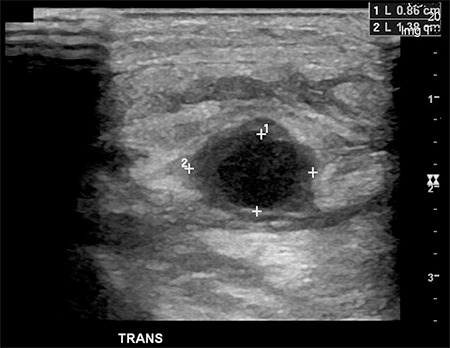

The patient was treated for sterile inflammation with ice and nonsteroidal anti-inflammatory analgesia. Two days later, his pain worsened and he presented to his primary care doctor. He was admitted to an outlying hospital where blood cultures revealed Staphylococcus aureus bacteremia. An arterial duplex showed a fusiform true aneurysm of the radial artery measuring a maximal diameter of 1.4 cm and a length of 1.5 cm (Figure 2 and 3). There was thickening of the aneurysm wall with no evidence of pseudoaneurysm or soft tissue abscess.

Figure 3. Axial plane ultrasound depicting radial artery fusiform aneurysm.